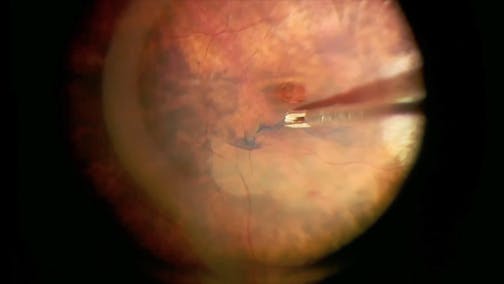

Retinal Detachment

Kazuaki Kadonosono, MD

Unpleasant Surprise

Stratos Gotzaridis, MD